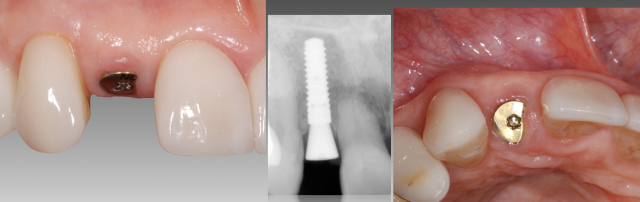

The treatment plan was to extract the lateral incisor and place a single tooth implant. (Fig. 2) At the time of implant placement, the facial was treated with contour augmentation to help preserve the facial hard/soft tissue esthetics. (Buser et al. J Dent Res, 2013, Jensen et al. J Perio 2014)

Three months after implant placement and confirmation of implant integration, an implant provisional was used to shape the soft tissue profile. (Fig. 4) Utilizing a custom impression coping, the exact soft tissue contours were transferred to the technician. (Fig. 5)